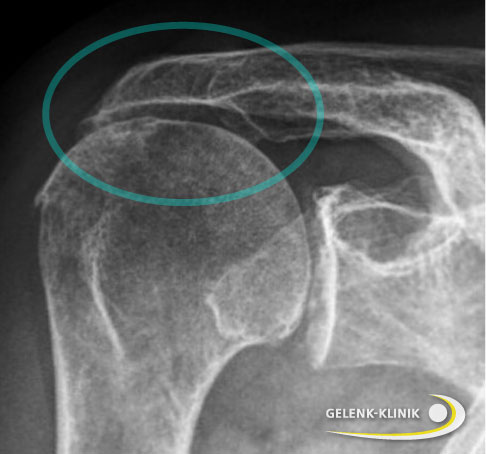

Auf Röntgenaufnahmen erkennt der Schulterspezialist die typische Verschmälerung des Gelenkspalts bei Omarthrose. Die primäre Schulterarthrose zeigt in vielen Fällen eine Knorpelabnutzung der hinteren Anteile der Gelenkpfanne. Osteophyten sind Zeichen einer fortgeschrittenen Arthrose. Im späten Krankheitsstadium kann der Oberarmkopf ebenfalls verformt (deformiert) sein.